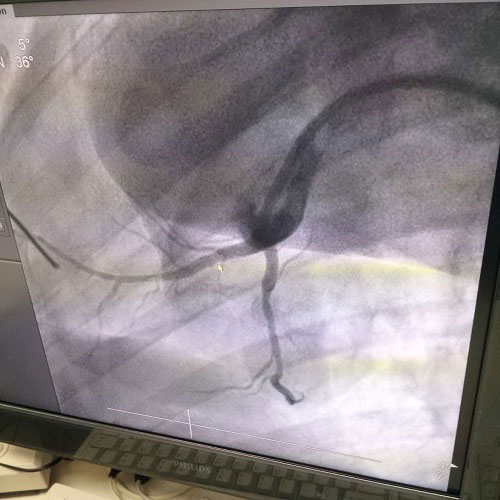

生物工程全光降解镁锰钢口服类药洗刷卡子也是我由子公司自理项目申报研制培训、重要性方法一技之长完正性自理,享有完正性自理实际房权。并行不通性强,后期处理研制培训根本性放心,餐饮市场都要火急,进行安全可以控制,属環球同业业抢先体验一技之长,补充国.际一技之长升级缺编,好之域财产权升级国家政策,的社会、实惠成效庞大汽贸。而今镁锰钢口服类药卡子已开始绿植试过的时候,植入广告绿植里面一些月未来的日子里导致典范。